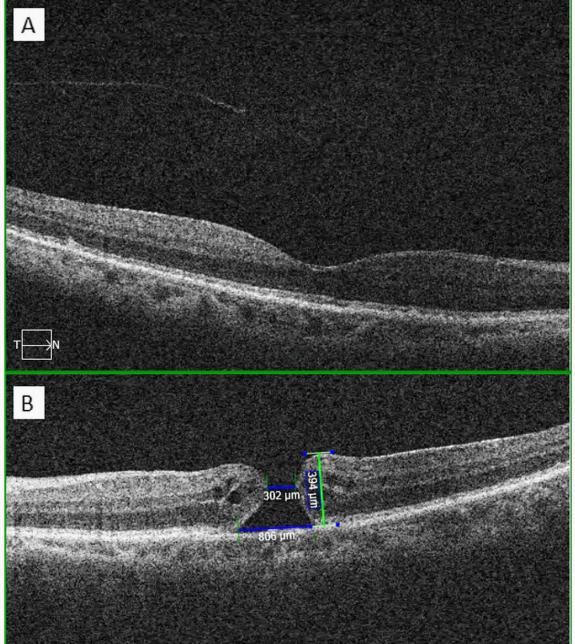

专科检查,最佳矫正视力为右眼0.5,左眼0.1。裂隙灯检查,双眼白内障,均为2级核。双眼眼压均为14 mmHg ,眼球运动和瞳孔光反射均无显著差异。眼底检查发现左眼黄斑裂孔。为了补充临床检查,医生进行了OCT扫描:右眼检查显示中心凹正常、局部玻璃体后脱离;左眼全层黄斑裂孔,Gass分类为2期(图1)。

▲图1 双眼黄斑OCT成像。右眼黄斑表现为正常的中心凹结果和局部玻璃体后脱离;B左眼黄斑表现为全层黄斑裂孔,内径302µm,外径806µm,高度394µm,可见小的视网膜内囊肿,无玻璃体牵拉。

研究表明,约6%的黄斑裂孔可能发生自发性闭合,通常发生在最初诊断后的3-4个月后。一些OCT特征可提示自发闭合:首先,裂孔直径小于400µm,特别是小于250µm更容易闭合;此外,玻璃体黄斑牵引缓解、在黄斑裂孔边缘形成桥状结构和囊肿也提示可能自发闭合。而刘奶奶的黄斑裂孔初始直径为302µm,未观察到玻璃体黄斑牵引,并存在小的视网膜内囊肿,这些特征均提示黄斑裂孔可自发闭合。